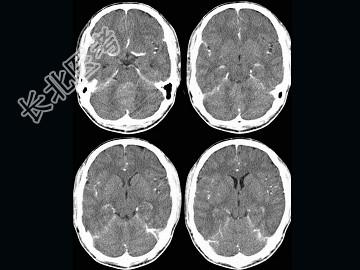

- 单项选择题男,16岁, 头痛、呕吐10天,CT检查, 最可能的诊断为 ( )

A、脑膜瘤

B、髓母细胞瘤

C、室管膜瘤

D、脑血管瘤

E、血管母细胞瘤